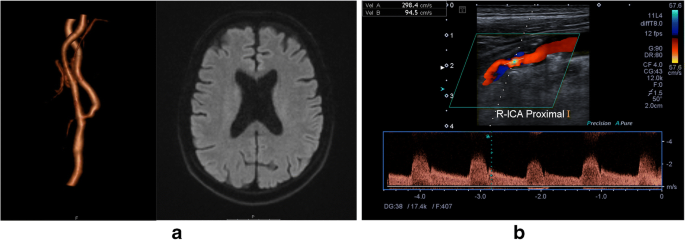

Normally, we offer cerebrovascular secondary prevention for patients in both in- and outpatient settings. The service provides consultations and comprehensive diagnostics. Neurosonography of brain-supplying arteries reveals pathologies such as vessel occlusions, stenoses (Fig. 1) or dissections that are correlated with other neuroimaging findings (multimodal magnetic resonance and/or computer tomography and/or digital subtraction angiography) performed at our tertiary stroke centre. Potential cardioembolism is investigated by bubble test and transcranial Doppler monitoring for detection of microemboli.

A 70-year old patient suffered an amaurosis fugax on the right side lasting for some minutes. On admission, his NIHSS score was 0. MR imaging (a) and neurosonography (b) revealed a moderate stenosis of the extracranial internal carotid artery on the right side due to atherosclerosis without any DWI lesion. He was obese, smoking and had arterial hypertension with hypertensive cardiomyopathy and coronary heart disease. Cardiac rhythm monitoring on the stroke unit did not reveal any relevant arrhythmia. Daily aspirin 100 mg and atorvastatin 80 mg were initiated and a carotid endarterectomy of the extracranial internal carotid artery on the right side performed on day 4. There was no complication. He was discharged home without any focal neurological deficits on day 6. He has been adhering to medications and has adapted his lifestyle since. No recurrent event has occurred for 1 year by now.